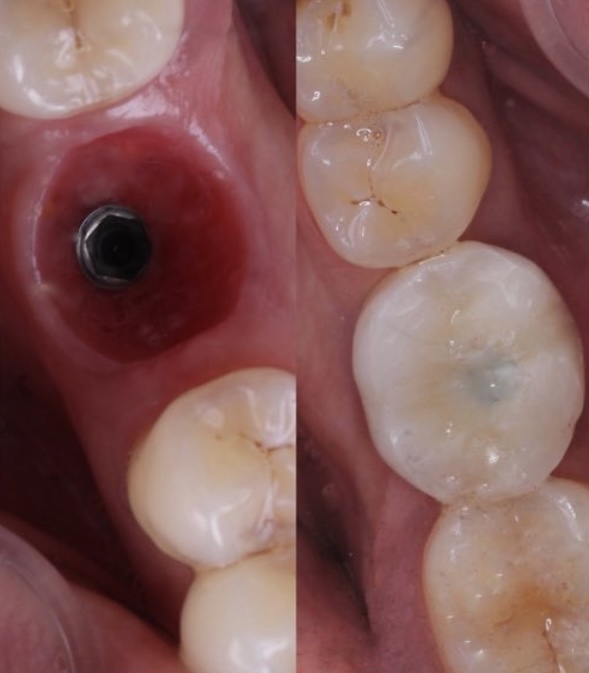

cirujano buco maxilofacial, armonizador orofacial e implantologo oral